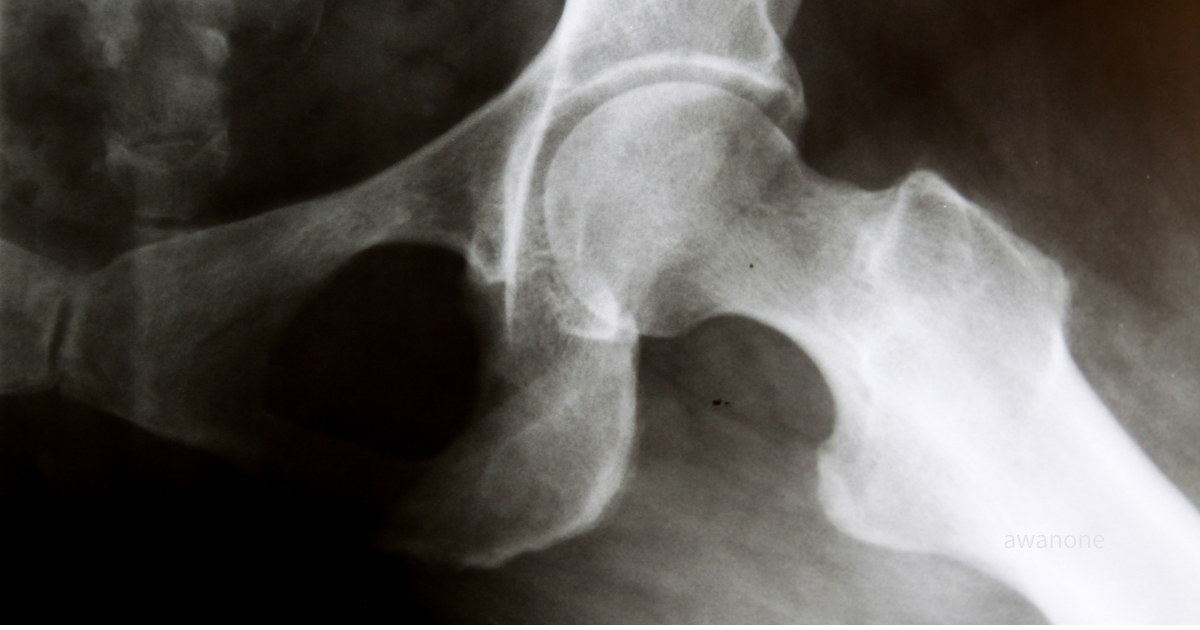

股関節変形と痛みは必ずしも一致しない

股関節痛の相談の中で、「レントゲンで変形していると言われた」と不安を抱く方は少なくありません。

しかし、臨床研究や疫学データをみると、画像上の変化と症状の強さは必ずしも一致しないことが分かっています。

レントゲン上で**軽度の変形(Kellgren–Lawrence分類1〜2)**を認めた人は、

男性で18.2%、女性で14.3%とされました(Nakamura K et al., Osteoarthritis Cartilage, 2015)。

ところが、そのうち実際に股関節痛を訴えた人はごく一部にとどまりました。

すなわち、「レントゲン上は変形があるのに、痛みを感じていない人」が相当数存在するということです。